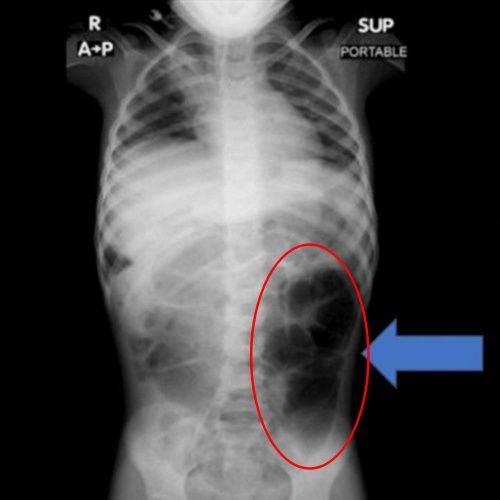

검사 결과 A양의 위 내부에서는 비정상적으로 큰 이물질이 발견됐으며, 의료진은 수술을 통해 이를 제거했다. 해당 이물질은 다량의 머리카락이 엉켜 형성된 덩어리로, 위에 머무는 데 그치지 않고 소장의 일부까지 길게 이어진 상태였던 것으로 확인됐다.

라푼젤 증후군은 머리카락을 뽑아 먹는 습관(발모식증·모발섭식증)으로 인해 위 안에 머리카락 덩어리가 생기고, 이 덩어리가 소장까지 길게 이어지는 매우 드문 질환이다.

동화 속 라푼젤처럼 길게 늘어진 머리카락 형태가 위에서 장으로 이어진 모습과 닮아 이 같은 이름이 붙여지게 됐다.

주로 청소년과 젊은 여성에게서 나타나며, 불안·강박·스트레스 등 심리적 요인과 동반되는 경우가 많다. 주요 증상으로는 복통·복부 팽만을 비롯해 구토·소화불량·체중 감소·식욕 부진 등의 증상이 일어나며, 심하면 장 폐색·출혈·천공까지 나타나게 된다.